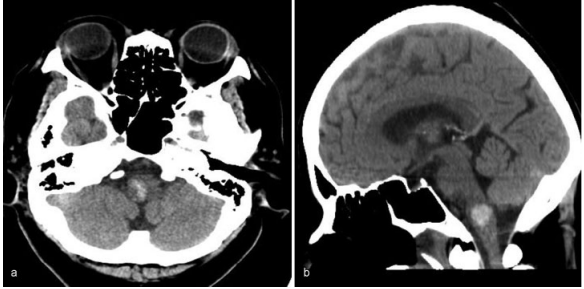

一位70岁的老人因为突然出现恶心和呕吐而被转诊到德国INI。右舌下神经麻痹导致右舌偏斜。她的血压是201/100毫米汞柱。电脑断层扫描(CT)显示右侧延髓出血

图:右侧延髓出血的电脑断层影像,(a)轴向(b)矢状面。